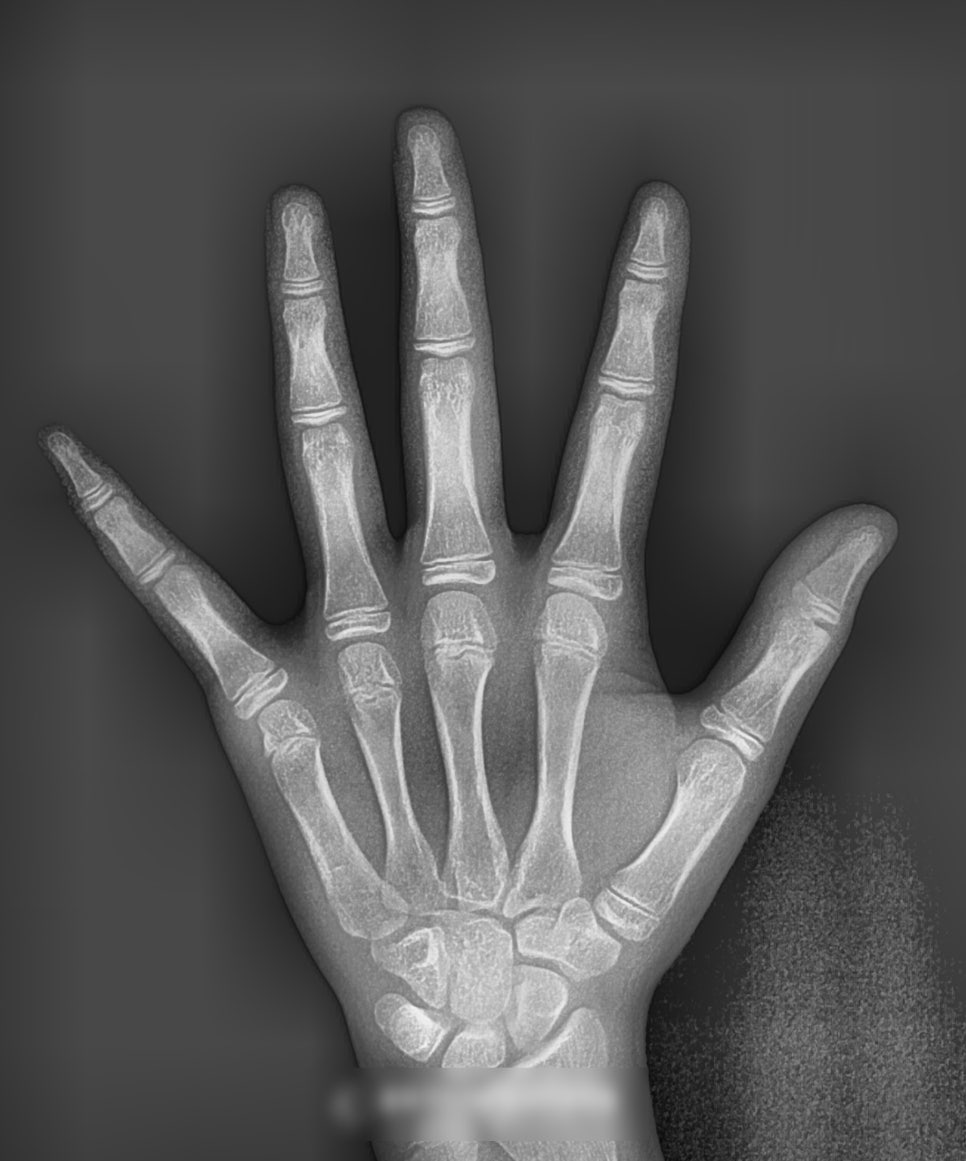

특히 이렇게 아직 성장을 진행 중인

어린이의 경우라면 더더욱 조기에

문제를 바로잡는 것이 중요합니다.

여러 검사를 통해

위아래 위치 관계 및 영구치 맹출 여부를 판단 후

주걱턱 치아교정 치료가 이뤄지는 게 좋습니다.